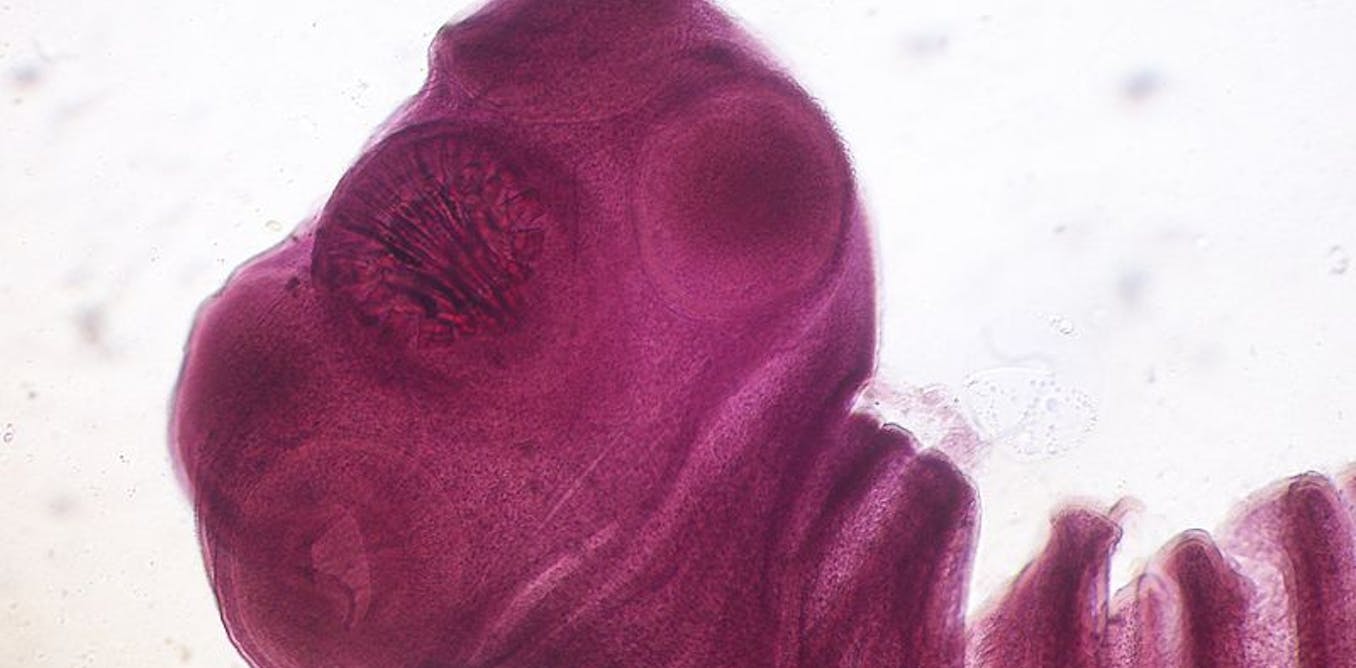

Этапы жизненного цикла тениид